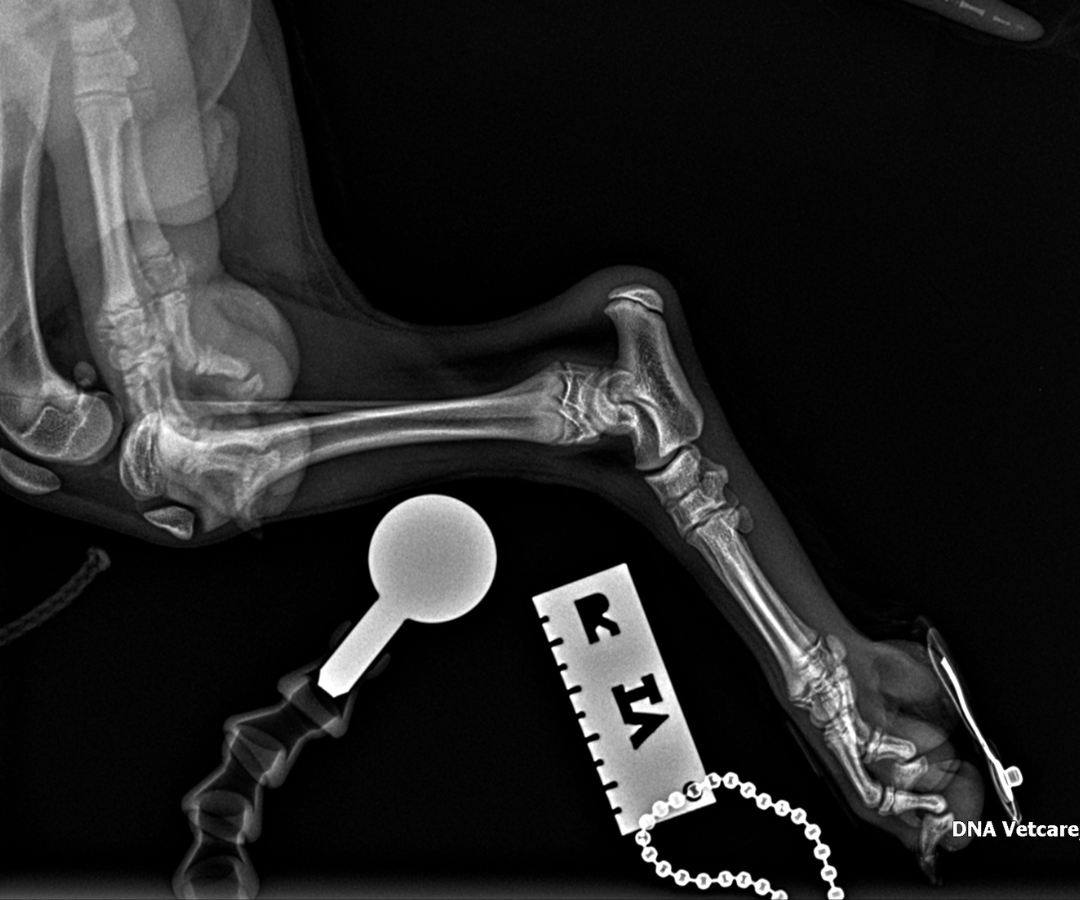

X-rays and cone beam CT of Ralphie's left hindlimb - a technique that uses a cone-shaped beam to produce detailed 3D images, particularly useful in complex orthopaedic cases like this - revealed a combination of injuries that, together, posed a serious surgical challenge:

- A comminuted fracture of the base of the left calcaneus (heel bone), meaning that the bone had broken into multiple fragments

- A small avulsion fracture in the calcaneoquartal region, whereby a small piece of bone had been pulled away from the joint when it was suddenly pulled by the long plantar ligament

- Dislocation of the talo-calcaneal joint - the lower ankle joint that connects the top ankle bone to the heel bone

- Plantar and lateral dislocation of the talocentral joint - this meant that the ligaments holding the bones in the hind leg together had completely torn, and the main hinge joint had broken, causing the paw to collapse toward the ground (plantar) and shift outward toward the side (lateral).